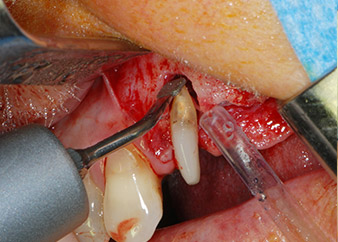

Un mois plus tard, le jour de l'intervention, la douleur et l'inflammation sur la dent 24 étaient minimes mais une mobilité de classe 2 de Miller était toujours observable. Après ouverture des lambeaux et nettoyage des tissus périapicaux et périradiculaires infectés, l'étendue du défaut osseux est devenue parfaitement visible (Figures 2 et 3).

À la racine de la dent, il manquait la totalité de l'os vestibulaire et distal. L'attache était essentiellement limitée à la racine palatine, venant ainsi confirmer le pronostic défavorable initial. La dent 27 présentait également une attache horizontale réduite et une raréfaction apicale minime (cf. Fig. 1), sans symptômes cliniques.

Nous avons toutefois maintenu notre projet initial de conservation des deux dents comme piliers temporaires d'un bridge pendant la période de six mois nécessaire à l'ostéointégration des implants. À la prochaine incision, la situation devrait être réétudiée. Premièrement, afin de gérer le problème endoparodontal, la surface de racine restante a été soigneusement débridée à l'aide d'un équipement piézoélectrique (Piezomed, W&H, utilisé avec l'insert en forme de spatule S1, initialement conçu pour limer la paroi sinusienne latérale) (Fig. 4).